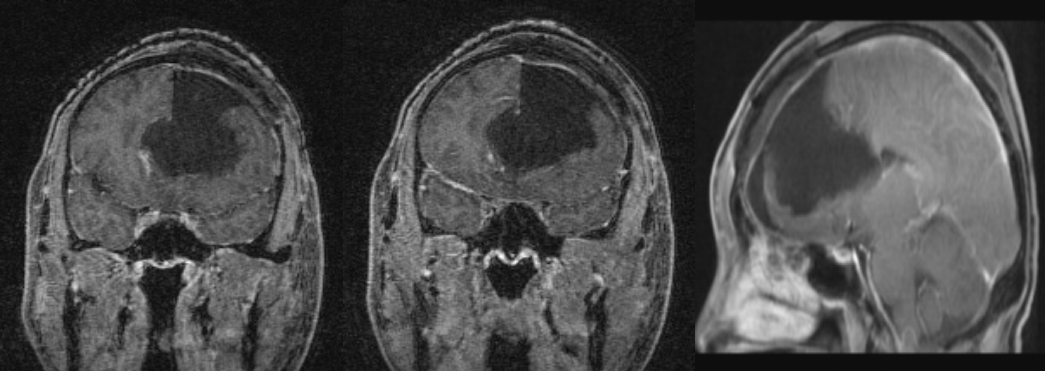

术后半年MRI增强